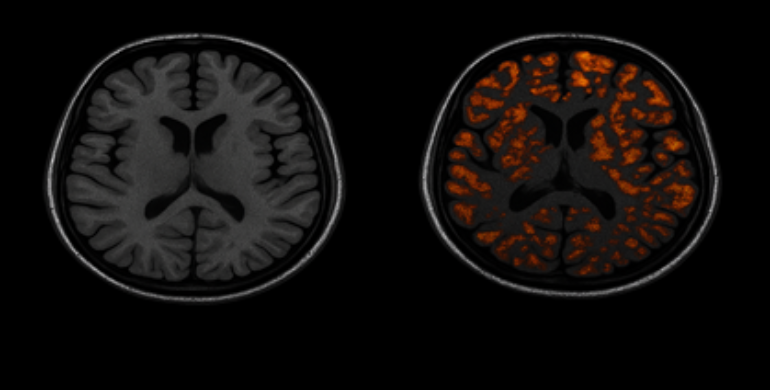

There was a short article about anosmia – loss of smell – as an early indicator of Alzheimer’s disease. Nothing unusual there, until I noticed the image they used: what appeared to be a generic stock image of a brain scan showing amyloid beta plaques, with no reference or explanation in the article. That struck me as strange.

First, a bit about the amyloid hypothesis. It was first championed in 1992 and posits that the accumulation of amyloid-beta protein in the brain is the primary driver of Alzheimer's disease. The plaques were thought to trigger the cascade of neurodegeneration and cognitive decline characterizing the disease.